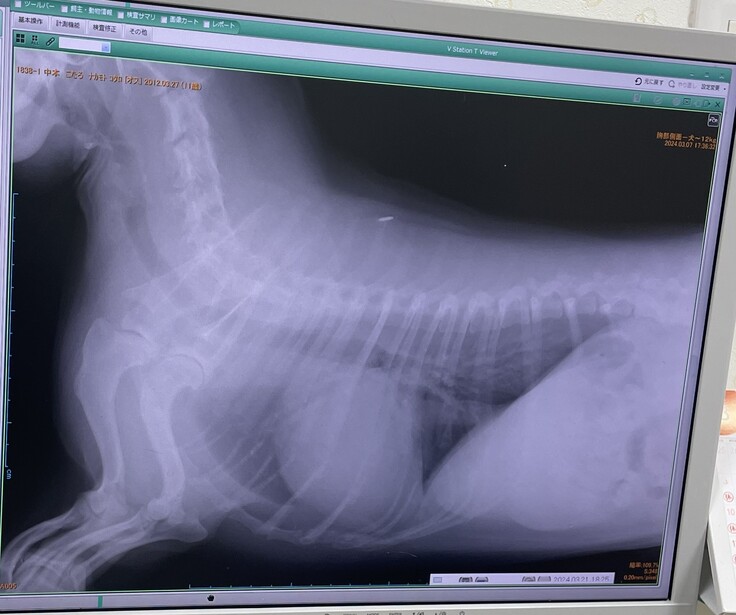

▼レントゲン

去年2月より心臓が大きくなっており肺・呼吸器が圧迫されていて咳が出る状態

(普通のわんこは真ん中に心臓があるが、こたろは左に寄っていて、

これが生まれつきなのかはわからないとの事)

※掲載画像はすべて病院からの許可をいただいています